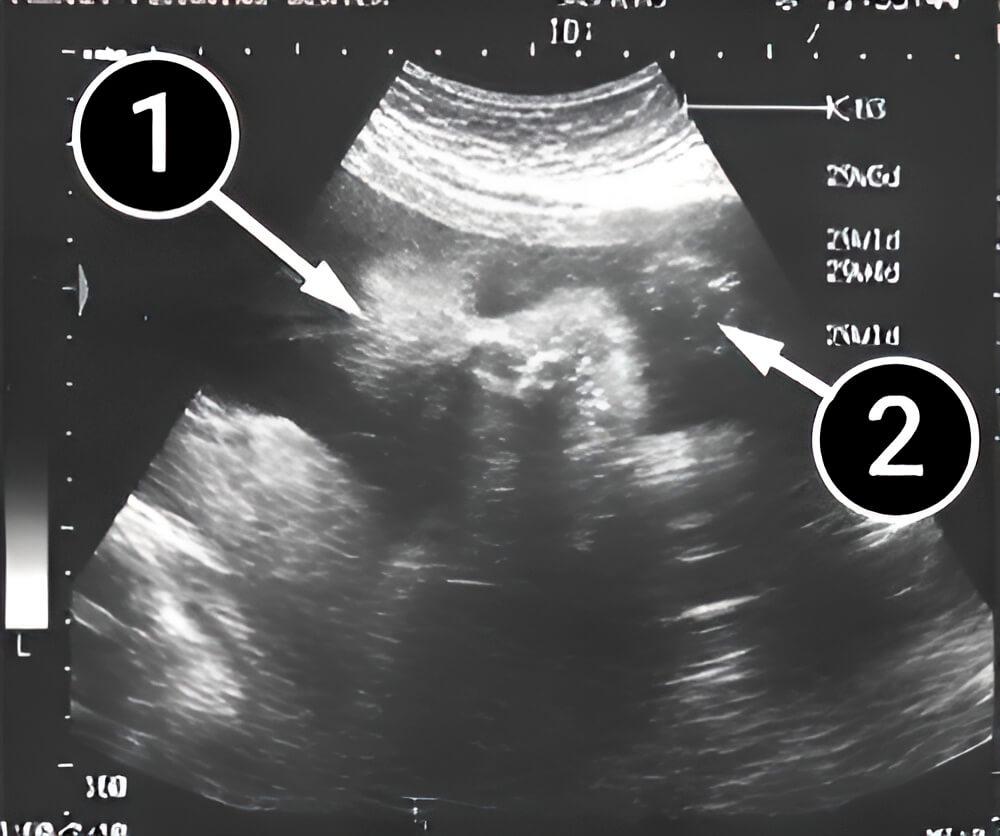

¿Qué se puede ver en la ecografía/ultrasonido?

La foto muestra un primer plano del rostro de un bebé. Está recostado sobre su lado derecho. Los rasgos faciales, incluidos los ojos y las pestañas, son visibles. En la foto, sus ojos están cerrados. La mano del bebé también es visible, extendida hacia adelante.